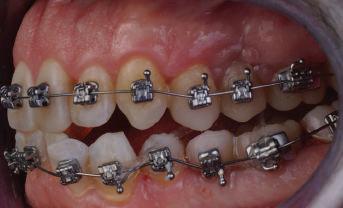

20 Dental Tribune Bulgarian Edition / октомври 2022 г. П ациентите със завършен растеж и скелетни проблеми обикновено представляват предизвикателство за ортодонт ската практика. Необходимостта от изваждане на зъби в комбинация с особеностите на възрастовата ортодонтия изисква особено внима ние. Фокусът върху критично важното значение на позицията на долните резци във връзка с дългосроч ната стабилност и постигането на оптимални оклузални взаимоотношения при затварянето на екстракционните пространства лесно може да излезе извън контрол. Когато към тези чисто кли нични проблеми се добави и стресът от натоваре ната практика, предизвикателството става още по-голямо. Всички тези фактори налагат използ ването на доказан подход с ясни и последовател ни стъпки, в което се разкрива силата на дисциплината „Алекзандър“ – предвидим протокол през целия процес на елиминиране на ротациите, ниве лиране на дъгите, затваряне на екстракционните пространства и финализиране на случая. Именно такъв е и случаят, който презентираме –екстракционен, скелетен клас 3 при възрастен па циент, лекуван по системата „Алекзандър“. ПРЕДВИДИМИ РЕЗУЛТАТИ ПРИ ПАЦИЕНТИ СЪС ЗАВЪРШЕН РАСТЕЖ И СКЕЛЕТЕН КЛАС 3, ИЗПОЛЗВАЙКИ ЕКСТРАКЦИОННО ЛЕЧЕНИЕ ПО ДИСЦИПЛИНАТА „АЛЕКЗАНДЪР“ Д-р Радой Димитров, България Преди започване на лечение клиничен случай | ортодонтия Фиг. 1а–1e Преди започване на лечение. Пациентът пристига в практиката с основното оплакване от невъзмож ност за нормално дъвчене. Снета е цялата необходима диагностична ин формация. Фиг. 1f–1h Снимки в профил и анфас. Фиг. 1i–1k Панорамна снимка, телерентгенография и анализ на телерент генография. Фиг. 1а Фиг. 1d Фиг. 1f Фиг. 1g Фиг. 1h Фиг. 1e Фиг. 1b Фиг. 1c Фиг. 1i Фиг. 1j Фиг. 1k

closed.

21Dental Tribune Bulgarian Edition / октомври 2022 г. ДИАГНОСТИЧНИ РЕЗУЛТАТИ: 1. Възраст на пациента: 21 години 2. Скелетен клас III (ANB 0) 3. Зъбен клас 3 4. Ръбцова захапка във фронта, кръстосана в дисталните участъци 5. Тясна горна челюст 6. Overjet – 0 мм, Overbite – 0 мм 7. Несъответствие на горната с долната средна линия 8. Единични контакти в ЦО 9. Хиподивергентен тип на растеж SN/MP – 33.5 10. Неравен гингивален контур 11. Неравна линия на усмивката 12. Тенденция за рецесии в долен фронт ПРЕПОРЪЧИТЕЛНО ЛЕЧЕНИЕ: Пълно ортодонтско лечение с метални брекети „Алекзандър“ Корекция на клас 3 захапката в областта на кучешките зъби с екстракция на първите пре молари в долна челюст Корекция на кръстосаната захапка в дистални участъци Коригиране на ръбцовата захапка във фронта Подобряване на ОJ и OB на пациента Стрипинг в долен фронт Подреждане на зъбите в горната и долната челюст Професионално хигиенизиране и профилактични дентални прегледи са препоръчителни на всеки 6 месеца. 1-ви месец След 1 месец са залепени брекети в горната челюст – поставена е еластична дъга. 016 NiTi. В долната челюст са елиминирани ротациите, поставена е стоманена дъга. 016SS, закалена с ток, и еластична верижка за затваряне на пространствата. 3-ти месец В долната челюст е поставена трета дъга – 17 x 25 NiTi с къси лигатури и верижка

В горната челюст се затварят пространствата с дъга .016SS и верижка. 5-и месец На 5-ия месец след залепяне на брекетите в долната челюст е поставена стоманена дъга 16 x 22 SS с четвъртито сечение, омега луп и тай бек. В горната челюст е поставена дъга 17 x 25 NiTi. Поради липсата на стабилни оклузални контакти са поставени лингвални верижки в областта на моларите, за да се предотврати нежелана ротация на 7-ите зъби. 6-и месец На 6-ия месец от началото на лечението са екстрахирани долните първи премолари, поставена е дъга 16 x 22 SS със затваряща чупка teardrop. Чупката се активира всеки месец по 1 мм с чинч-бек. клиничен случай | ортодонтия СТЪПКИ НА ЛЕЧЕНИЕТО Начало на лечението Лечението започва с поставяне на апарат за бърза експанзия в горната челюст. През първия месец от лечението са направени 24 оборота на апарата за експанзия. Залепени са брекети в долната челюст, поставена е дъга 17x25 CuNiTi, като са предпи сани клас 3 ластици (1/4”,4 1/2 oz) по време на сън, за да се осигури контрол върху торка на долните резци. Фиг. 2а Фиг. 3a Фиг. 4a Фиг. 3b Фиг. 4b Фиг. 3c Фиг. 4c Фиг. 3d Фиг. 4d Фиг. 3e Фиг. 4e Фиг. 5a Фиг. 5b Фиг. 5c Фиг. 5d Фиг. 5e Фиг. 6a Фиг. 6b Фиг. 6c Фиг. 6d Фиг. 6e Фиг. 7a Фиг. 7b Фиг. 7c Фиг. 7d Фиг. 7e Фиг. 2b Фиг. 2c Фиг. 2d